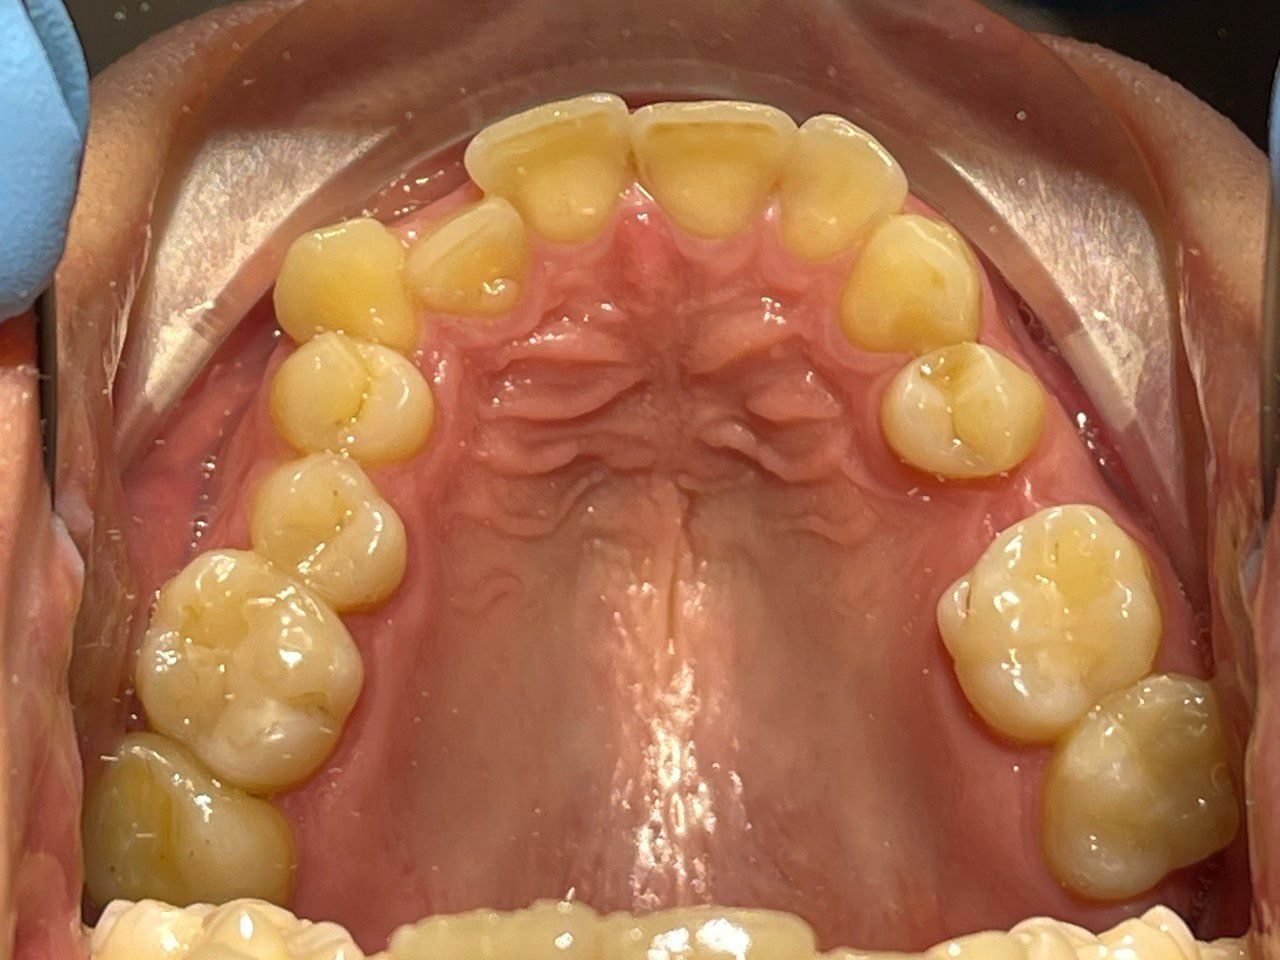

Выявленные проблемы

• Дистальная окклюзия

• Дефицит апикального базиса

• Сужение зубных рядов

• Вестибулярное положение клыков

• Скученность во фронтальных и боковых отделах

Брекет-система Pro